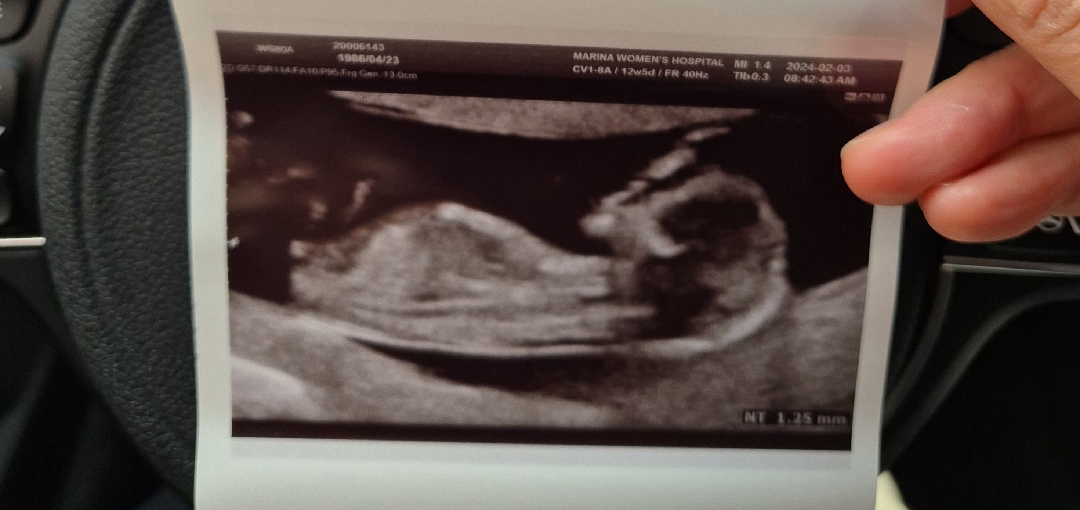

각도법 12주5일

아들일까요 딸일까요?

딸인거같아요~

딱 딸같네요 오아

공주님 하잇😄

저도 딸에 한표요! ㅎㅎ